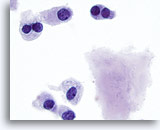

Bij de monsters in deze categorie geldat dat bij resectie in bijna 100% van de gevallen een maligniteit wordt gevonden. Papillair carcinoom is de meest voorkomende maligniteit van de schildklier en heeft specifieke nucleaire kenmerken die eenvoudig zijn vast te stellen bij cytologische monsters. Andere maligniteiten waarvan de diagnose zeer nauwkeurig kan worden vastgesteld op basis van cytologie, zijn onder andere medullaire carcinomen, lymfomen, en metastatische carcinomen. Papillair carcinoom wordt gekenmerkt op ThinPrep door lagen en papillaire clusters van opeengepakte cellen met kernvergroting en molding, poederige chromatine, onregelmatige kerncelmembranen (met name kerngroeven en intranucleaire cytoplasmische inclusies), en kleine maar prominente en vaak eosinofiele nucleoli.[7] Daarentegen wordt medullair carcinoom gekenmerkt door geïsoleerde monomorfe plasmacytoïde cellen, die een hoge kern/cytoplasma-ratio hebben, excentrische kernen en grofkorrelige chromatine met of zonder een prominente nucleolus. Kleine, onopvallende granulen vullen het cytoplasma. Soms lijken de cellen spoelvormig, maar vertonen ze dezelfde nucleaire kenmerken. Lymfomen en metastatische carcinomen van de schildklier komen veel minder vaak voor. Hun cytologische kenmerken hangen af van het type en de plaats van oorsprong.